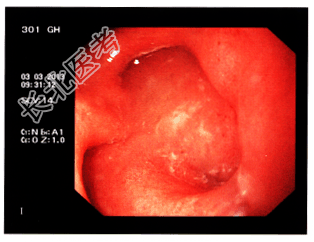

- 简答题3、禁食、输液1天后胃镜检查结果见下图。目前诊断考虑哪些疾病